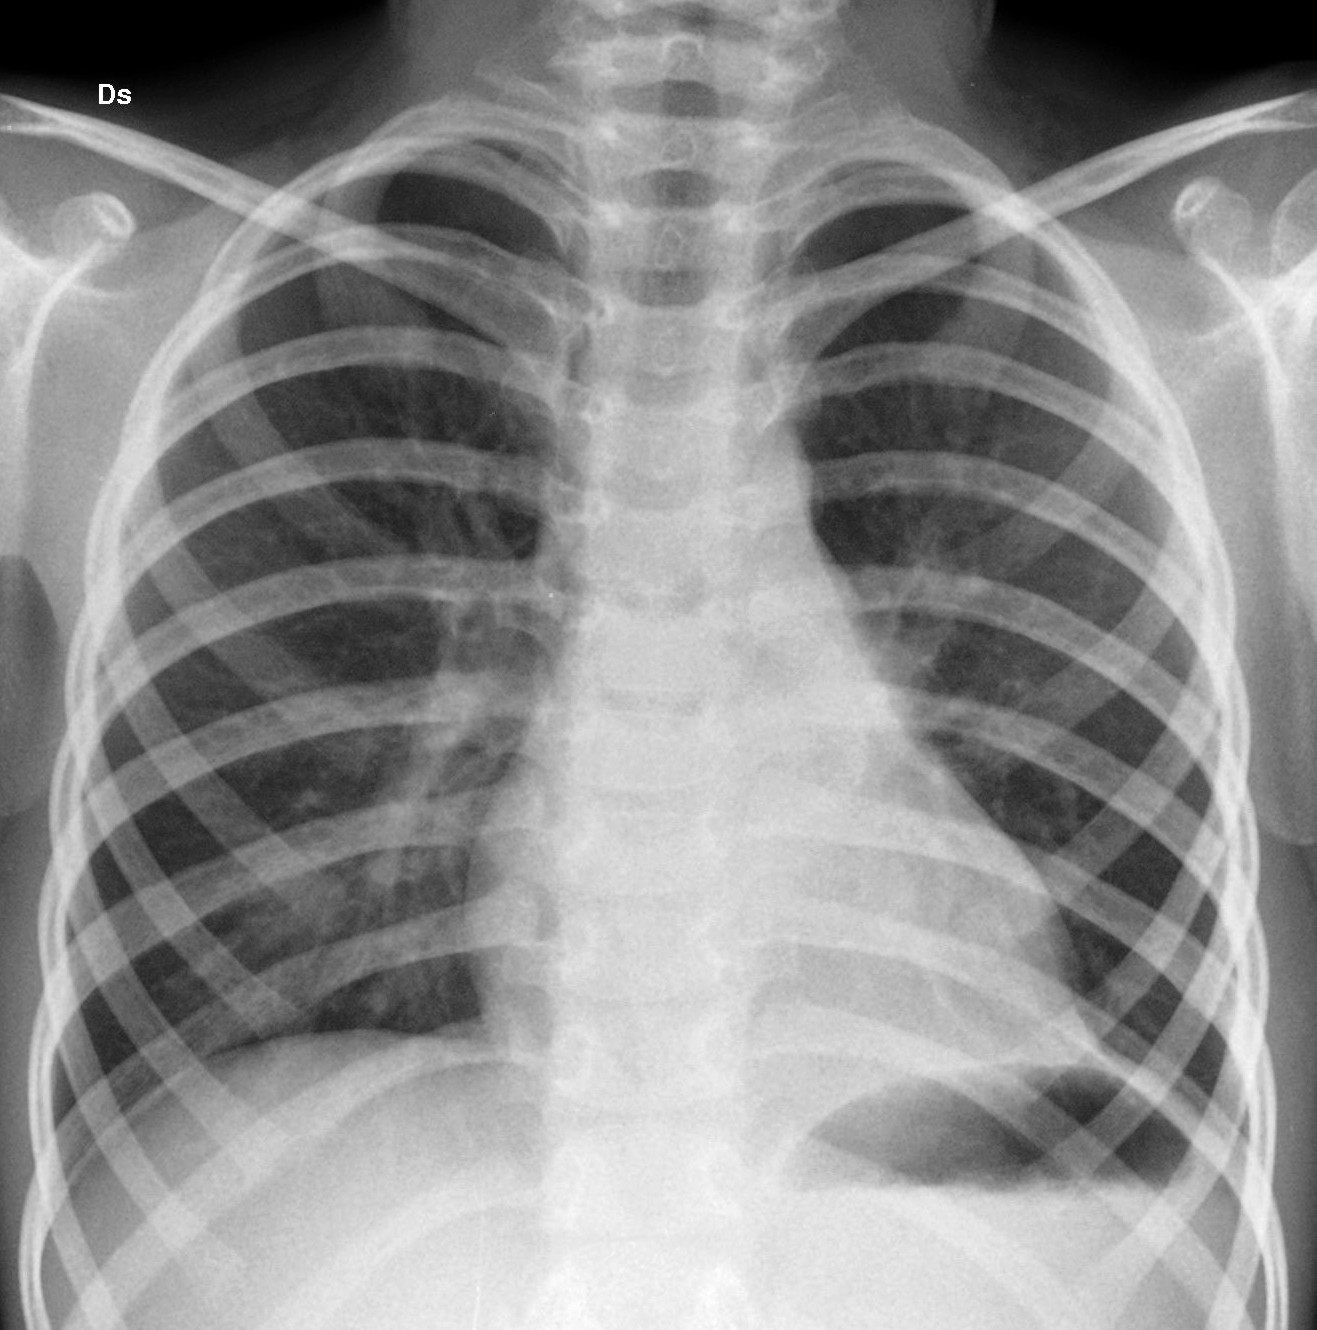

In Figura 3 l�immagine del controllo a un anno dall�intervento.

Figura 3 |